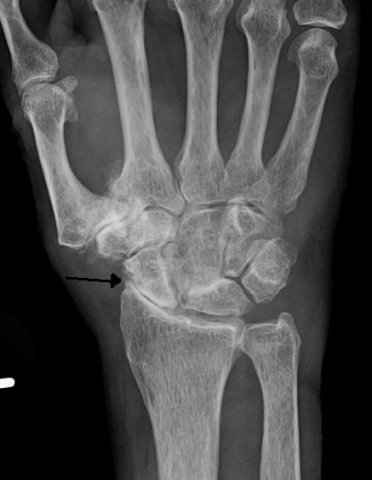

Konsekwencją tego przewlekłego procesu zapalnego jest nieodwracalne zniszczenie stawów, które ulegają deformacjom i odkształceniom, a w końcu trwałemu unieruchomieniu.